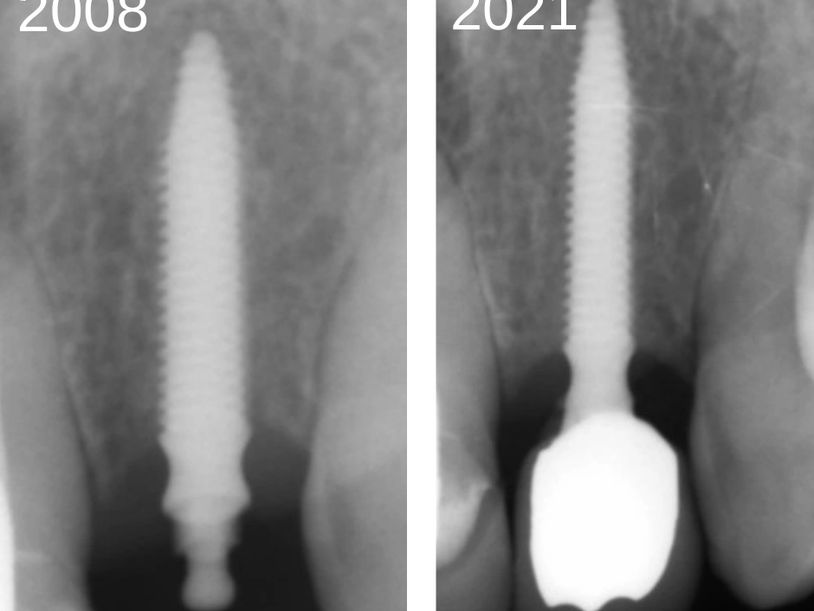

Surgical or "Conventional" Dental Implants came into vogue in the mid 1980's and have been the only method taught to graduate dentists since then. These implants require surgery to open the gum, drill a deep wide channel in the jawbone before placing a titanium screw. A temporary denture can be worn if required but generally not necessary if it is a back tooth. Anywhere between 3-6 months later, the implant surface is uncovered by opening a window in the gum and connecting a second stage, known as the "abutment" before creating the final porcelain crown.

Having performed numerous such procedures between 1984 and 2003, in our clinic we have found that the same results are achievable WITHOUT SURGERY and WITHIN A FEW WEEKS, rather than months. Using our KEYHOLE techniquie there is no need to wear a removable denture as we create a temporary tooth at the first visit and usually complete the final porcelain crown a few weeks later.

All of these refinements in the implant technique we use results in substantially less time and cost for our patients and is accompanied by virtually zero pain after the procedure.